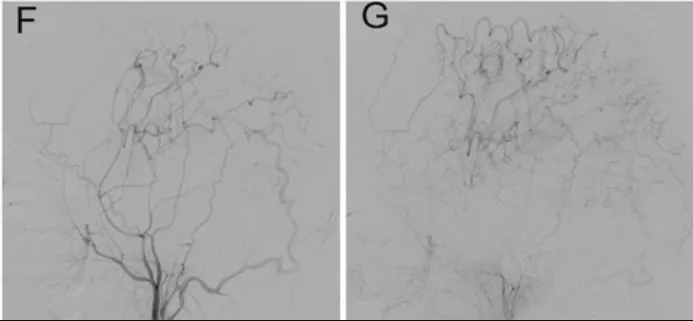

所幸手术取得圆满成功。术后复查显示新建“枕动脉-大脑中动脉”通路通畅,小智的头痛、视力模糊及肢体无力症状完全消失;单光子发射计算机断层扫描(SPECT)显示其大脑中动脉及大脑后动脉供血区的“脑血管反应性”(CVR)显著提升——表明大脑应对血流变化能力增强,未来缺血风险大幅降低。

术后6个月随访DSA显示旁路血管通畅(图F、图G)。